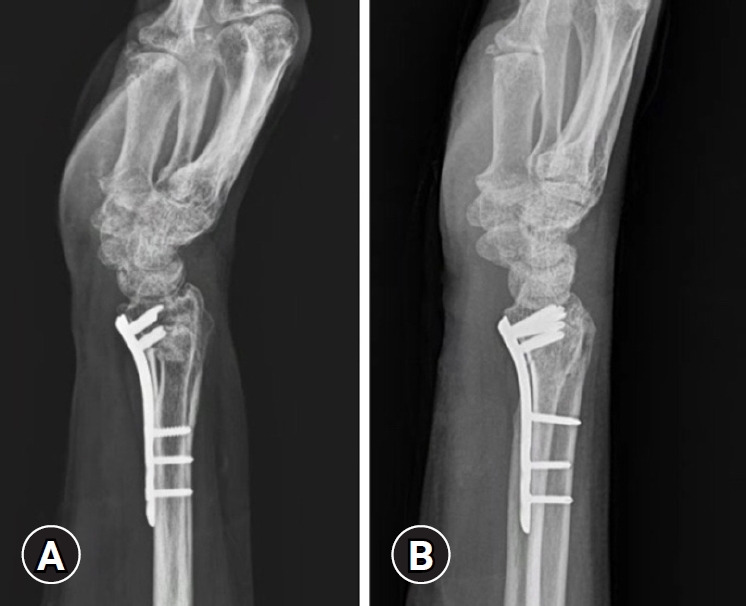

Methods: From January 2010 to December 2022, a total of 185 patients aged 60 years or older with AO type C distal radius fractures who were treated with a volar locking plate at our hospital were enrolled. Of these, 59 patients were excluded according to the study criteria, resulting in a final cohort of 126 subjects. Without differentiating between left and right sides, group A (n=60) underwent distal locking screw fixation with screws of 12-mm length (except for the most radial screw) using near-cortex-only drilling. In group B (n=66), drilling was performed through to the dorsal cortex, and the length was measured using a depth gauge; distal screws were then fixed at a length 2 mm shorter than the measured depth. The degree of fracture reduction on postoperative radiographs was assessed using the modified Lidstrom scoring system by measuring radial inclination, radial height, and volar tilt. In addition, the visual analog scale, the Korean Disabilities of the Arm, Shoulder, and Hand (DASH) score, and the incidence of extensor tendon rupture and tenosynovitis were evaluated at the final follow-up and compared between groups.

Results: Bone union was achieved in all cases, with no significant radiographic differences observed between the two groups (P>0.05). In contrast, two cases of extensor tenosynovitis were noted in group A, whereas group B experienced one extensor tendon rupture and five cases of extensor tenosynovitis, representing a significant difference (P<0.05).

Conclusions: In patients aged 60 years or older with AO type C distal radius fractures, the technique of near-cortex-only drilling with short distal locking screws yielded satisfactory results for fracture reduction and clinical indices. This approach may offer a new alternative for preventing extensor tendon rupture or tenosynovitis.